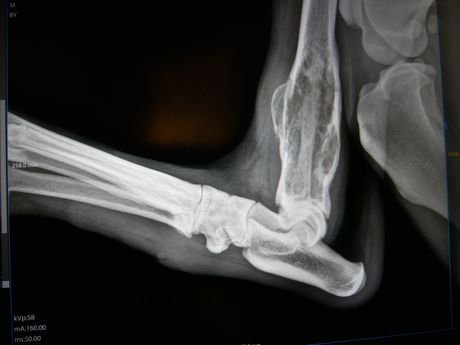

Digital røntgen

Vi har digital røntgen av svært godt kvalitet som gjør det mulig å undersøke smertetilstander som halthet og diagnostisere beinbrudd, artrose og fremmedlegeme blant annet.

Vi tilbyr også AD/HD røntgen med innsending til NKK.